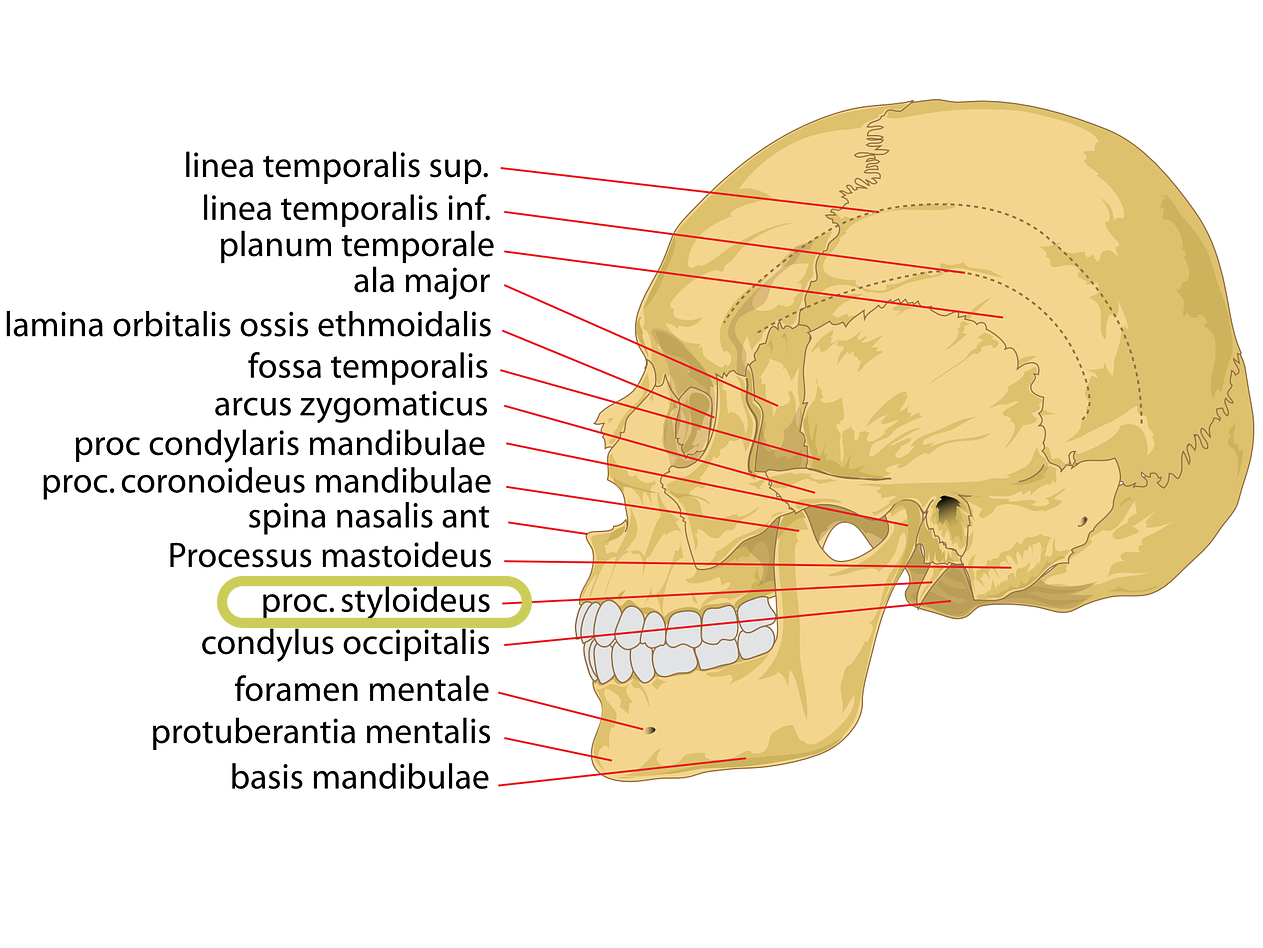

Das Eagle-Syndrom wurde erstmals 1949 beschrieben. Wenn ein bestimmter Knochen an der Schädelbasis (der Processus styloideus) zu lang entwickelt ist, kann dieser wichtige Nerven und/oder Blutgefäße beeinträchtigen. Zu den Symptomen gehören:

- die innere Jugularvene, A. carotis interna

- der Nervus glossopharyngeus

- Nervus vagus

- Nervus accessorius

- Arteria occipitalis

- Nervus hypoglossus

- Nervus trigeminus